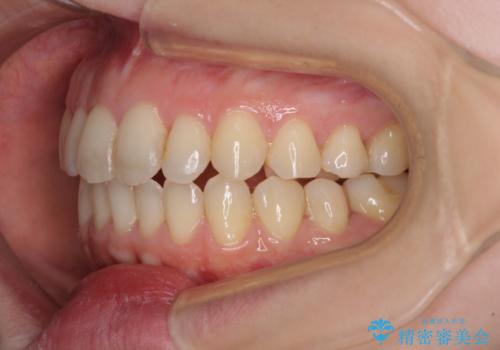

- 前歯のデコボコを気にして来院された患者様です。

下顎が骨格的にずれており、上下正中を合わせることは難しいことが予想されたため、デコボコの解消を主目的として、ワイヤー矯正を行うこととしました。

治療途中で出産されたこともあり、当初予定よりも終了までに期間がかかってしまいました。

舌を前方に突出する癖があったため、上下前歯がなかなか接触しなかったことも治療期間が伸びた要因です。